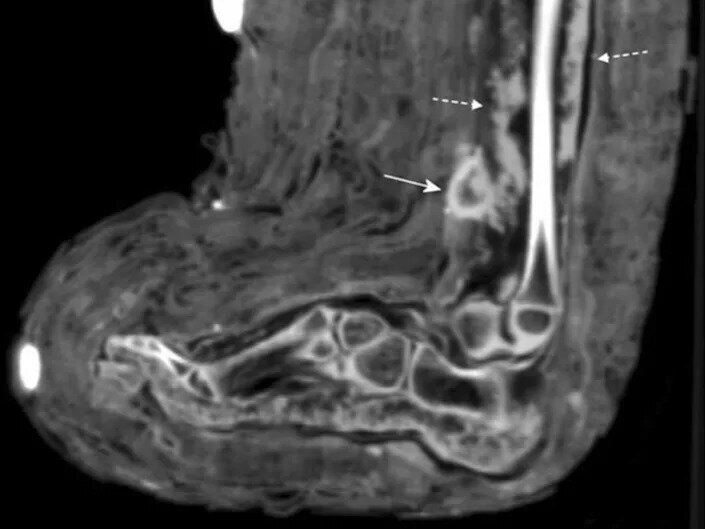

در سیتی اسکن مومیایی پانسمان زخم با «فلش پیوسته» و چرک درون زخم با «فلش مقطع» نشان داده شده است.

زینک و همکارانش هنگامی در حال انجام سیتی اسکنهای معمول بر روی مومیاییها بودند، این پانسمان را کشف کردند. سیتی اسکن نشانههایی از وجود چرک را هم در زخم نشان میداد.